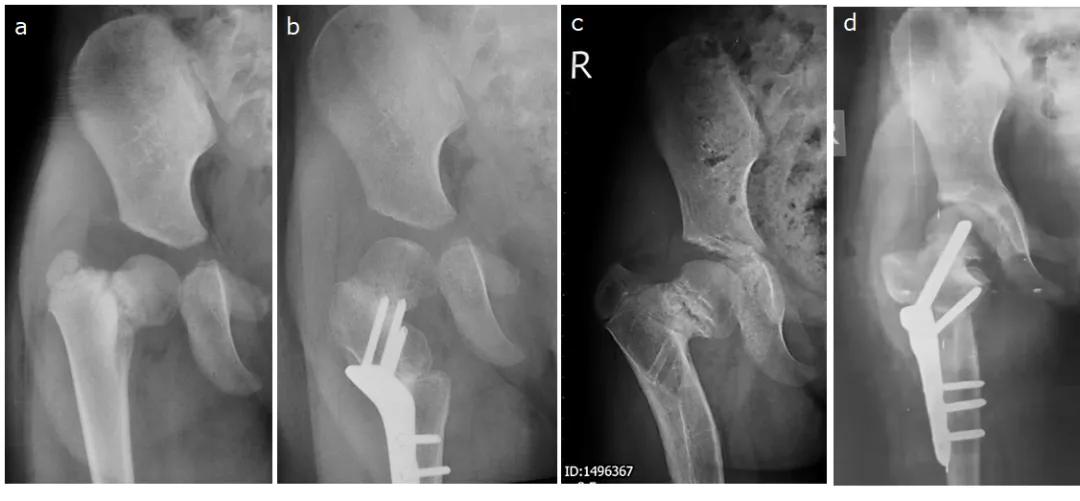

女孩,7岁时当地医院检查发现右侧先天性髋内翻畸形,测量HE角64°(图11a),行股骨近端外翻截骨术,采用150°钢板固定,术后截骨远端内移(图11b)。术后2年髋内翻复发(图11c)。行股骨近端外翻截骨翻修术,以140°php固定,截骨端为端-侧对合,固定后股骨近端形态更接近正常生物力学结构(图11d)。